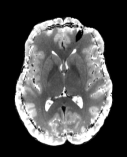

Reversed Gradient Polarity (RGP) methods are commonly used to correct susceptibility artifacts in Echo-Planar Imaging (EPI) [Stehling et al., 1991]. RGP methods acquire a pair of images with opposite phase encoding directions, which leads to a minimal increase in scan time due to the speed of EPI. In a post-processing step, RGP approaches use the fact that the distortion in both images has an equal magnitude but acts in opposite directions to estimate the field map (see Figure 1) [Chang and Fitzpatrick, 1992, Bowtell et al., 1994]. The field map is then used to estimate a distortion-free image.

Figure 1: The Reverse Gradient Polarity correction paradigm. Two images are acquired with opposite phase encoding directions, +v𝑣+v and v𝑣-v. These two images are used to estimate the field map b𝑏b, and the distortion correction model [Chang and Fitzpatrick, 1992] is applied to obtain a corrected image \mathcal{I}.